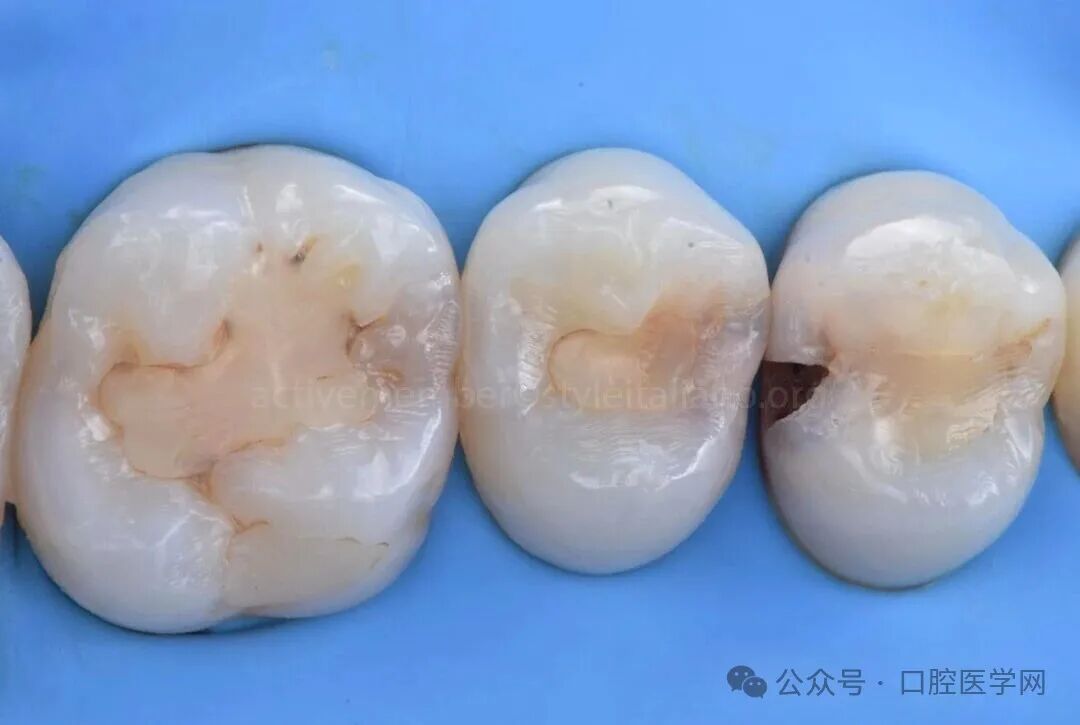

图6

当前文献报道的龋坏去除方式存在差异,从完全去腐至选择性保留牙本质不等。本病例中,龋坏去除至硬质牙本质层,以保障可靠的粘接效果。